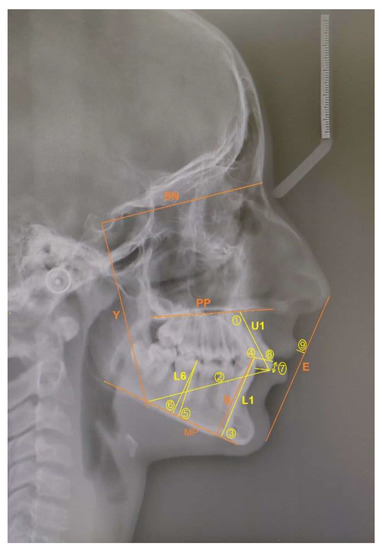

Inclusion criteria were growing patients with bilateral Class II malocclusion (ANB > 4°) due to mandibular retrognathia (SNB < 78°) with overjet (>4 mm) and deep bite (>4 mm), with no previous orthodontic treatment. Patients with developmental syndromes and anomalies (alveolar cleft and/or palate), mandibular fracture or deformities were also excluded from the study. A Class II malocclusion due to retrognathic mandible was identified through cephalographic analysis, so before-treatment (T0) and after-treatment (T1) lateral cephalograms (LC) were mandatory for all the patients. All lateral cephalograms (LC) were taken using the same equipment (Planmeca Promax, Helsinki, Finland) by an experienced dental radiology engineer under standard conditions: subjects were in the standing position and adequately protected, the Frankfort horizontal plane parallel to the floor, with the teeth in the maximal intercuspation (centric occlusion) and relaxed lips and tongue and with identical distances for each patient from the focus to the median sagittal plane of the subject’s head and to the film. Cephalometric analysis was performed for each patient before (T0) and after (T1) treatment. Definitions of the used (clinically important) angular and linear measurements are described and shown in Figure 1 and Figure 2. The linear and angular measurements were measured to the nearest of 0.1 mm and 0.1 degrees, respectively. Only the data with statistically significant changes before and after treatment are presented.

Legends: SNB: the angle formed between the SN plane and the point B indicates the relationship of the mandibular basal arch to the anterior cranial base; SNPg: the angle formed between the SN plane and the point Pg; ANB: the difference between SNA and SNB angle relates jaws to anterior cranial base; Wits appraisal: linear distance between the projecting points A and B perpendicular on the functional occlusal plane (AO and BO) indicates the skeletal sagittal jaw relationship; Gonial angle: the angle between the posterior tangent line of the ramus and the mandibular plane; LAFH: Lower anterior face height is the distance between points Sna and Me; CoGn: the linear distance between the condylion and the gnathion points indicates the mandibular length.

Figure 1. The angular and linear skeletal measurements.